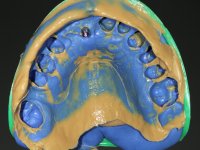

Primeira Fase

Foram feitas as extrações das raízes dos dentes 2.1 e 2.2 porque estavam a incomodar. Após 3 meses de cicatrização fez-se o exame imagiológico e estudo implantar para colocação do implante no local do 2.1.Foi colocado um implante de 4.1mm de diâmetro por 10mm de altura, colocado ao nível ósseo. Passados 2 meses após a cirurgia implantar, foi feita a segunda cirurgia para colocação de um parafuso de cicatrização. Foi feita a impressão ao implante com técnica de moldeira aberta com silicone de dupla viscosidade um mês após. No laboratório foi confecionada uma infraestrutura metálica para uma ponte de 2 elementos aparafusada ao implante. Esta infraestrutura apresentava 2 apoios palatinos para ajudar a estabilizar os dentes 1.1 e 2.3 a recuperar do traumatismo. Recuperados os dentes, os apoios poderiam ser retirados. Esta peça apresentava uma conexão interna ao implante com sistema anti-rotacional. A prova da infraestrutura foi feita em boca sendo o seu correto ajuste verificado com controle imagiológico. No revestimento da infraestrutura foi utilizada cerâmica de tonalidade coronária e gengival. Depois de verificada em boca e aprovada pelo paciente a ponte foi apertada definitivamente e o orifício de acesso obturado.